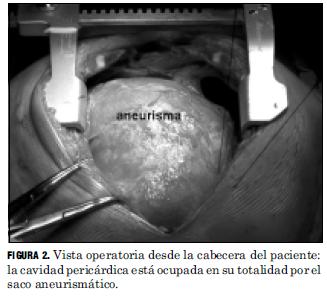

Una vez abierto el pericardio laxamente adherido a la pared anterior del aneurisma, se observó dilatación aneurismática de aorta ascendente de 15 cm de diámetro externo que ocupaba toda la cavidad pericárdica, no visualizándose las cavidades cardíacas que se encontraban desplazadas y laminadas hacia atrás y a la izquierda (Fig.2). Se colocó una segunda cánula venosa en aurícula derecha para desgravitar las cavidades cardíacas y aumentar el retorno venoso así como una sonda de aspiración en aurícula izquierda con el fin de descomprimir las cavidades izquierdas.